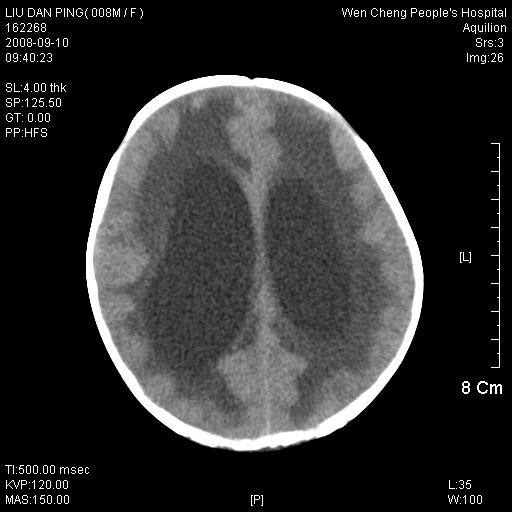

以下是引用卜一在2008-9-10 16:21:00的发言:[br]髓母细胞瘤伴梗阻性脑积水!支持![br]髓母细胞瘤特点:—般直径大于3.5cm,位于后颅凹中线之小脑蚓部。累及上蚓部的肿瘤延伸到小脑幕切迹之上,ct平扫肿瘤多呈均匀一致的高或等密度病灶,增强检查呈均匀一致的强化。病灶中有小坏死时,平扫亦可呈不均匀之混杂密度,注药后有增强。[br]

以下是引用zjzjr在2008-9-10 15:09:00的发言:[br]髓母细胞瘤伴梗阻性脑积水.